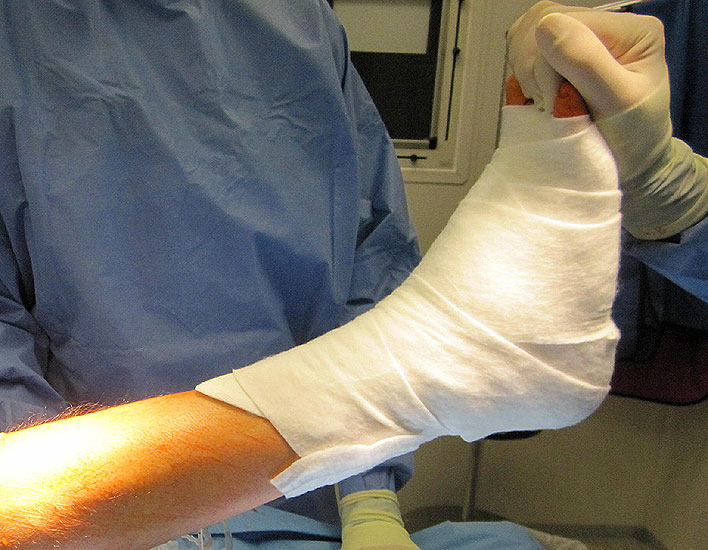

• Die Fersen des Patienten sollen mit dem Tischende abschließen (Abb. 3)

1. Wundheilungsstörung infolge einer hohen intraoperativen Druck- und Zugbelastung auf den periartikulären Weichteile; Lösung: dosierte Weichteilbehandlung durch die Hacken durch den Assistenten; aktive Erinnerungen während der Operation (Abb. 20 und 21)